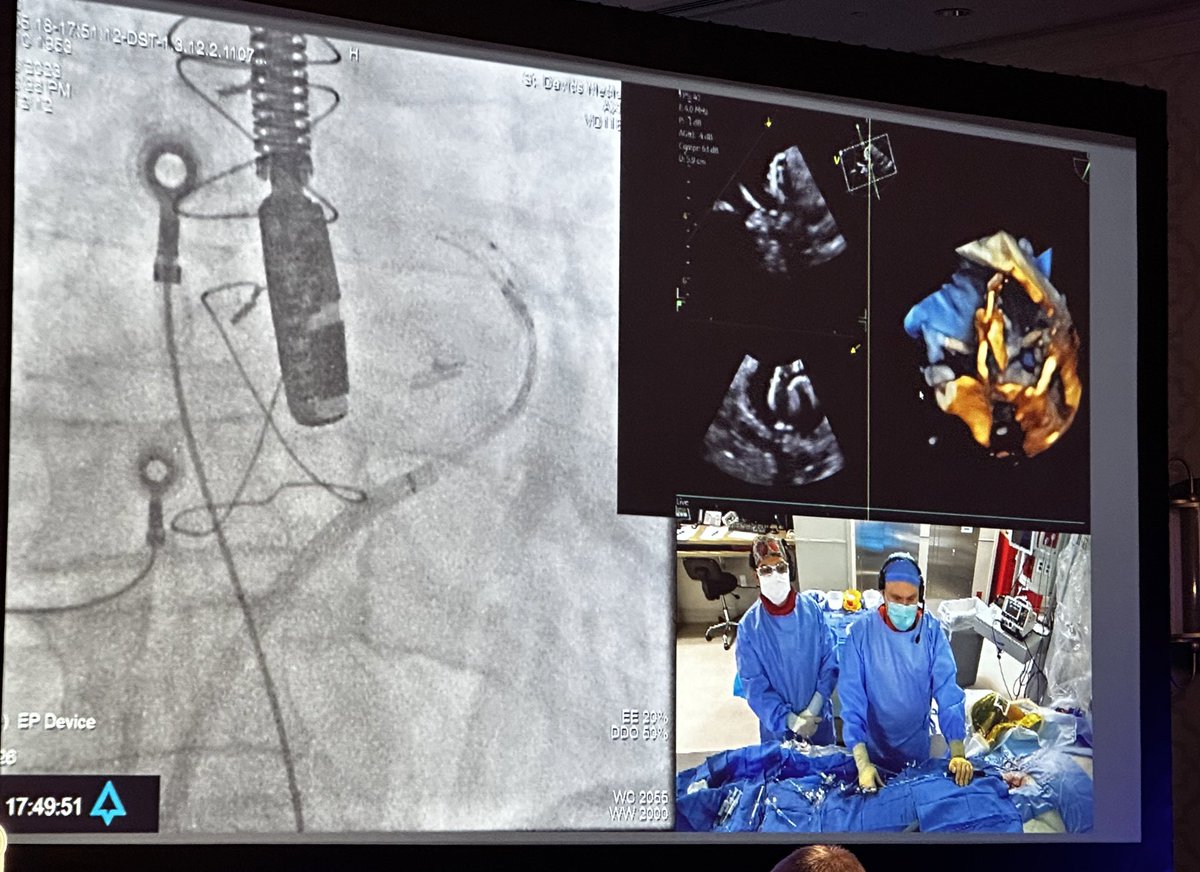

Live case from @tcainstitute leak closure for LAAO device. #SPAF2023 #HRS23 @RPHortonMD